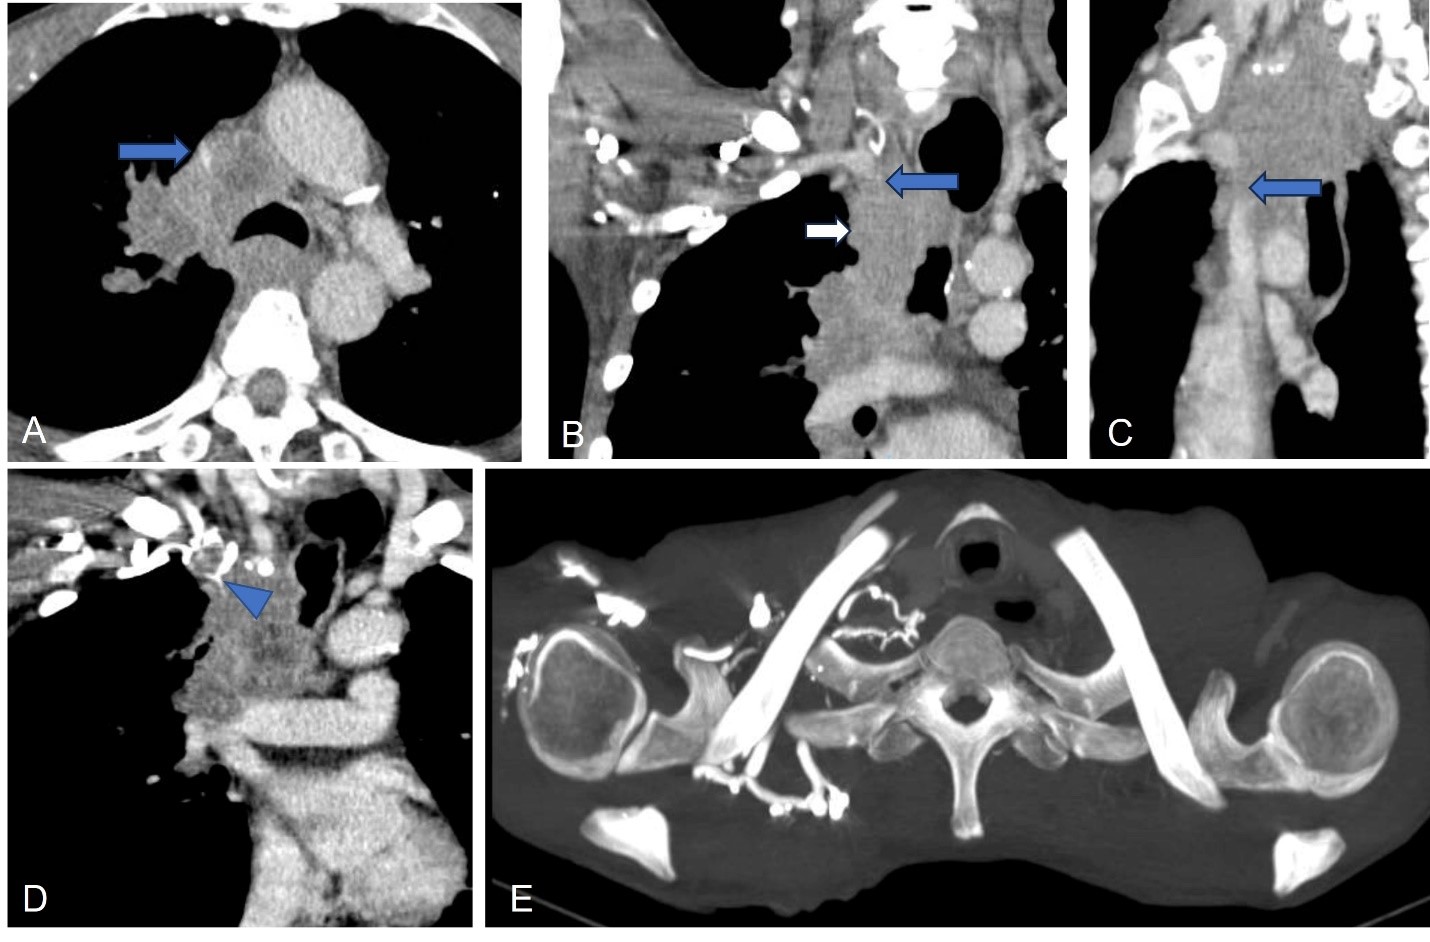

Siêu âm đàn hồi mô

Siêu âm đàn hồi mô (Elastography) là một ứng dụng khá mới của siêu âm chẩn đoán nhằm khảo sát đặc tính đàn hồi của mô trong cơ thể.